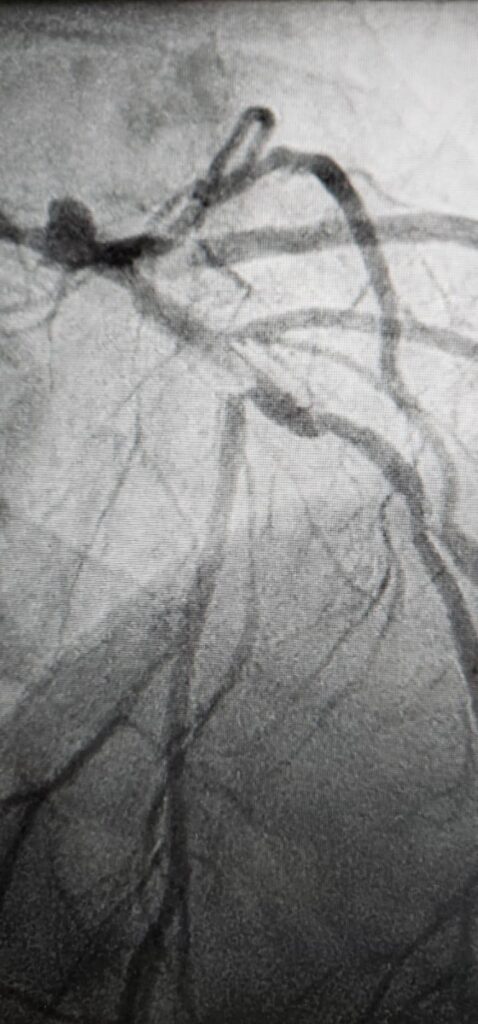

Rotoblācijas metodes princips ir mehāniski noārdīt šos cietos kalcija nogulsnējumus. Artērijā tiek ievadīts speciāls urbis, kas, griežoties ar lielu ātrumu, izveido “tuneli”, atbrīvojot asinsvadu. Pēc cietā slāņa noņemšanas un asinsvada elastīguma atjaunošanas, procedūru var turpināt ar balona paplašināšanu, bieži vien kombinējot ar ultraskaņas litotripsiju (kalcija šķelšanu ar ultraskaņu), un stenta implantāciju.

Galvenā rotoblācijas priekšrocība ir spēja efektīvi sagatavot artēriju stenta implantācijai, kas samazina komplikāciju risku un novērš asinsvada atkārtotu sašaurināšanos ilgtermiņā.